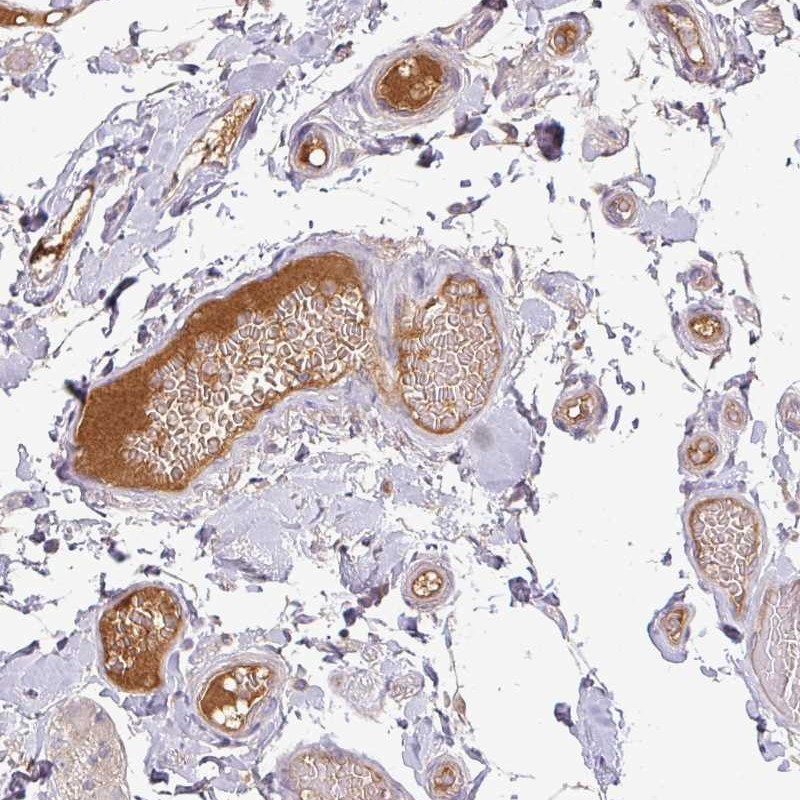

Immunohistochemical staining of human small intestine shows positivity in plasma.